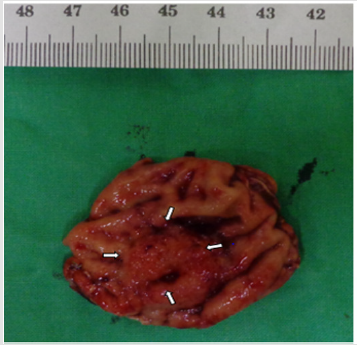

A 55-year-old woman without known systemic disease underwent a physical check-up in May 2014. Basic laboratory studies gave normal values (Hb: 12.3gm/dL, WBC: 7100/μL, INR: 1.09). Besides, liver and renal functions as well as levels of tumor markers including CEA, CA199, alpha-fetoprotein were within normal limits. There were no abdominal discomfort, no nausea or vomiting, no weight loss or other discomfort recently. No hypertension or diabetes mellitus were found in her family history. She was allergy to pyrine. No surgical history was found. On the other hand, PET scan showed increased Fludeoxy Glucose (FDG) uptake over the greater curvature of the stomach (Figure 1). Endoscopic gastroduodenoscopy revealed a reddish tumor with central depression about 1cm over the greater curvature of midbody (Figures 2a & 2b). Endoscopic ultrasound study demonstrated focal thickening of muscular layer with loss of layering over the first, second and third layers (Figure 3) for which biopsy was taken. Pathologic analysis showed chronic inflammation with infiltration of lympho-plasma cells. The initial impression was Gastrointestinal Stromal Tumor (GIST) or leiomyoma. After discussion with the pathologist, IMT was diagnosed. We discussed with patient about treatment for this tumor. The patient agreed to receive therapeutic endoscopy for tumor resection. After a futile attempt of local endoscopic resection due to technical problem, surgical intervention of subtotal gastrectomy with gastroduodenostomy was performed (Figure 4). After stabilization of general condition, the patient was discharged with regular follow-ups at the outpatient clinic. There was no evidence of tumor recurrence after following the patient for 24 months by endoscopic gastroduodenoscopy and PET scan. No adverse and unanticipated events were found during follow-up.

The final diagnosis was IMT which was origin from Muscularis propria layer.